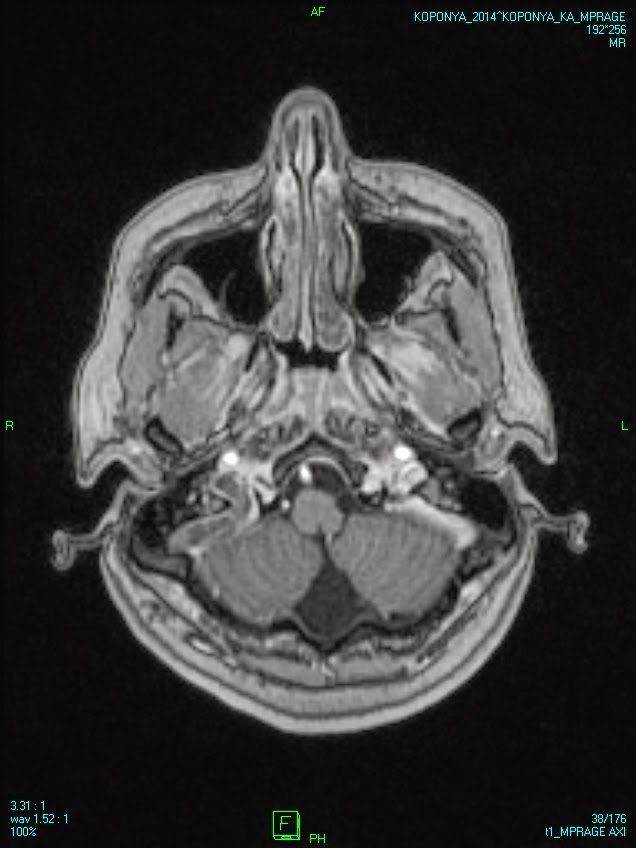

Dural venous sinus thrombosis Szerző: admin | szept 10, 2014 | Brain, Vascular | Nincsenek hozzászólások oral contraceptive in the medical history widened right transverse sinus without total obstruction affected sigmoid sinus on the right 00000815444